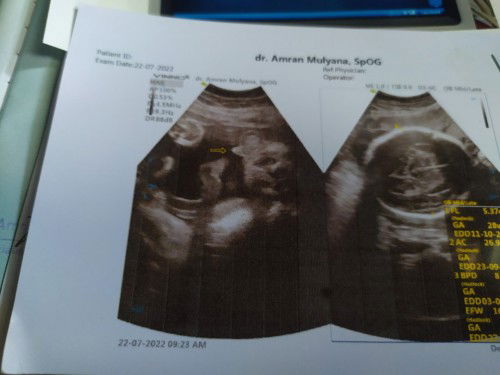

Bayi sungsang

Kemarin USG bayi sungsang kehamilan 30M hamil pertama, minta doanya supaya bayinya bisa muter bun aminn😞